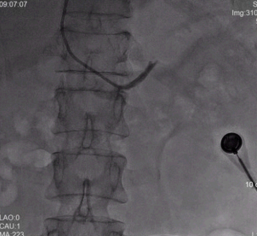

右侧、左侧肾上腺静脉取血示意图

而证明的方法,需要双侧肾上腺静脉取血术,这项微创的介入检查,仅仅国内仅少数几家医院能开展,我院就是其中之一。在充分的术前准备后,彭峰主任、方周菲和蔡瀚主治医师在介入手术室,成功为陈奶奶进行双侧肾上腺静脉取血术。取血结果证明,陈奶奶左侧肾上腺腺瘤存在大量分泌醛固酮的功能,这为手术治疗提供了最为充分且必要的证据。